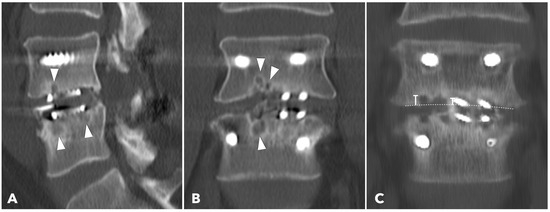

Lumbar spine computed tomography (CT) with 3 mm thin-slice coronal and sagittal reconstructions was performed one year after the surgery. Fusion status was assessed using the Bridwell grading system based on bone window images (Figure 4). Grades I and II were defined as successful fusion. Cage subsidence was defined as sinking > 2 mm beyond the bony endplate [24,30]. The presence of subchondral osteolysis was also recorded as a potential indicator of pseudoarthrosis (Figure 5).

Subchondral osteolysis was significantly more frequent in the MISTLIF group (52.9% vs. 13.3%, q < 0.001). Cage subsidence was also significantly more prevalent in the MISTLIF group (13.7% vs. 5.0%, p = 0.023), although most patients in both groups exhibited no evidence of subsidence (Table 5). Again, the statistical significance was no longer significant after applying the Benjamini–Hochberg correction to control the FDR.

Figure 5. (A,B) 1-year CT reconstruction revealed the presence of subchondral osteolysis or endplate cyst formation (white arrowheads). (C) The measurement of cage subsidence on the coronal CT reconstruction image.